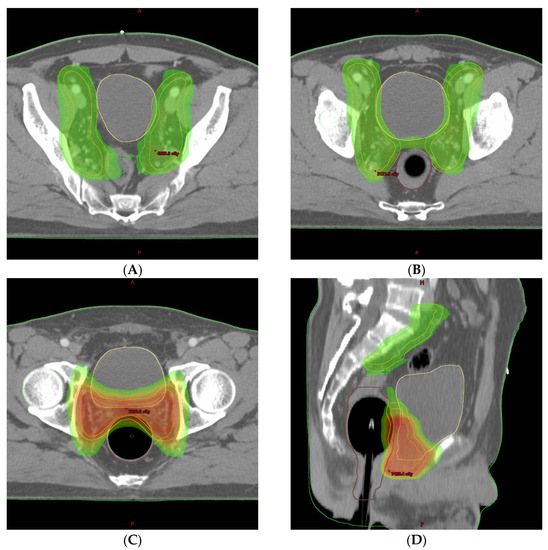

2. Detailed Case Description